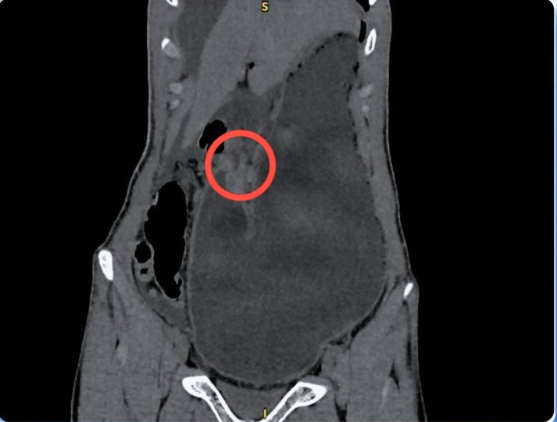

Hình ảnh CT cho thấy bệnh nhân bị thủng ổ loét môn vị tá tràng - Ảnh BVCC

Tại khoa Cấp cứu, các bác sĩ ghi nhận cơn đau không thuyên giảm, bệnh nhân toát mồ hôi, bụng chướng. Qua thăm khám và chụp CT-scan ổ bụng, kết quả cho thấy có nhiều khí và dịch tự do trong ổ bụng, dạ dày giãn lớn, thành hang môn vị dày bất thường và chỉ số bạch cầu tăng cao.

BS.CKII Nguyễn Vũ An – Trưởng khoa Ngoại Tổng quát chẩn đoán bệnh nhân bị viêm phúc mạc toàn thể do thủng ổ loét môn vị tá tràng và hẹp tá tràng hoàn toàn – một cấp cứu ngoại khoa nguy hiểm, đe dọa trực tiếp tính mạng nếu không phẫu thuật kịp thời.